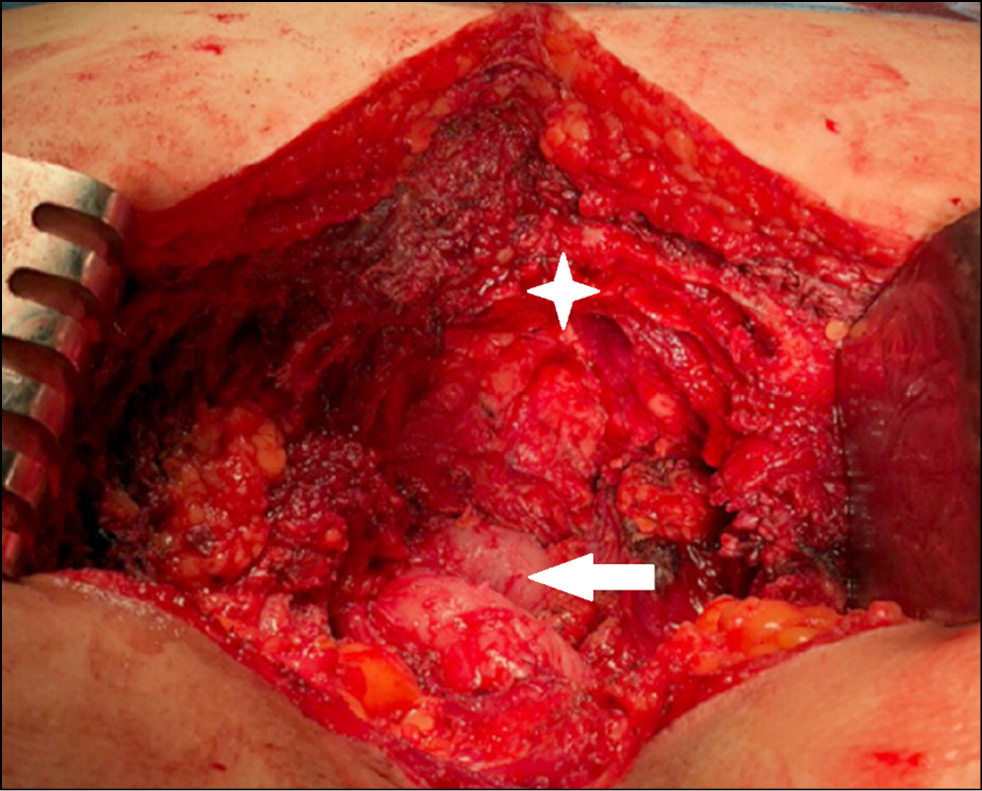

Under endotracheal anesthesia, anterior access was performed in the supine position. A lower midline laparotomy was then performed to mobilize the intestinal loops and ablatively mobilize the tumor from the surrounding tissues and the anterior surface of the proximal sacrum to the S3 level (Fig. 4). Provisor sutures were applied to the anterior abdominal wall, and the patient was then turned to the face-down position for posterior midline access to the sacrum and coccyx (Fig. 5).

Fig. 4. Anterior approach stage, colon exposure.

An electroligating instrument was used to cross the lumbar and large and middle gluteal muscles. A laminectomy was performed at the S3 vertebral level, and the dural sac was isolated. Two ligatures were applied below the S3 roots, and the cauda equina was tied and crossed between the ligatures. Bioclay was used to treat cauda equina and prevent liquorrhea. To gain access to the small pelvis, the ligaments and muscles were surgically removed from the coccyx. The rectum was then mobilized bluntly and acutely from the tumor along the anterior surface of the sacrum. By using a high-speed bur, the posterior elements at the S3 level were resected, and the anterior section was osteotomized at the same level using a chisel. The specimen was removed as a single block and sent for routine morphological examination (Figs. 6–8).

Fig. 6. Posterior view of the wound after tumor removal. The image visualizes the edge of the resection of the sacrum at the S3 level (asterisk), rectum (arrow).